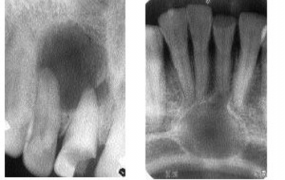

Όταν ένα δόντι νεκρωθεί από τερηδόνα ή τραύμα, τα μικρόβια και οι τοξίνες τους περνάνε από το ακρορρίζιο και προσβάλλουν το κόκκαλο τοπικά, που αρχίζει να απορροφιέται. Αυτή η βλάβη ονομάζεται ακρορριζικό κοκκίωμα και ακτινογραφικά έχει ακανόνιστα όρια.

Μερικές φορές υπολείμματα επιθηλιακών κυττάρων που υπάρχουν εκεί ενεργοποιούνται και δημιουργείται κύστη. Αυτή είναι ένας σάκος που περιέχει υγρό. Με την πάροδο του χρόνου η κύστη μεγαλώνει και κατατρώει το κόκκαλο της γνάθου( πιέζει και προκαλεί απορρόφηση). Μεγάλες κύστεις της κάτω γνάθου έχουν οδηγήσει σε κάταγμα.

Μερικές φορές η κύστη προκαλεί ενδοστοματικά μία διόγκωση. Αν γίνει από τον οδοντίατρο παρακέντηση και αναρρόφηση, συλλέγεται ένα υποκίτρινο υγρό. Αυτό επιβεβαιώνει τη διάγνωση κύστης. Στην ακτινογραφία βλέπουμε μία περιγεγραμμένη αλλοίωση, αν και μερικές φορές η διάκριση μεταξύ κοκκιώματος και κύστης δεν είναι σαφής.